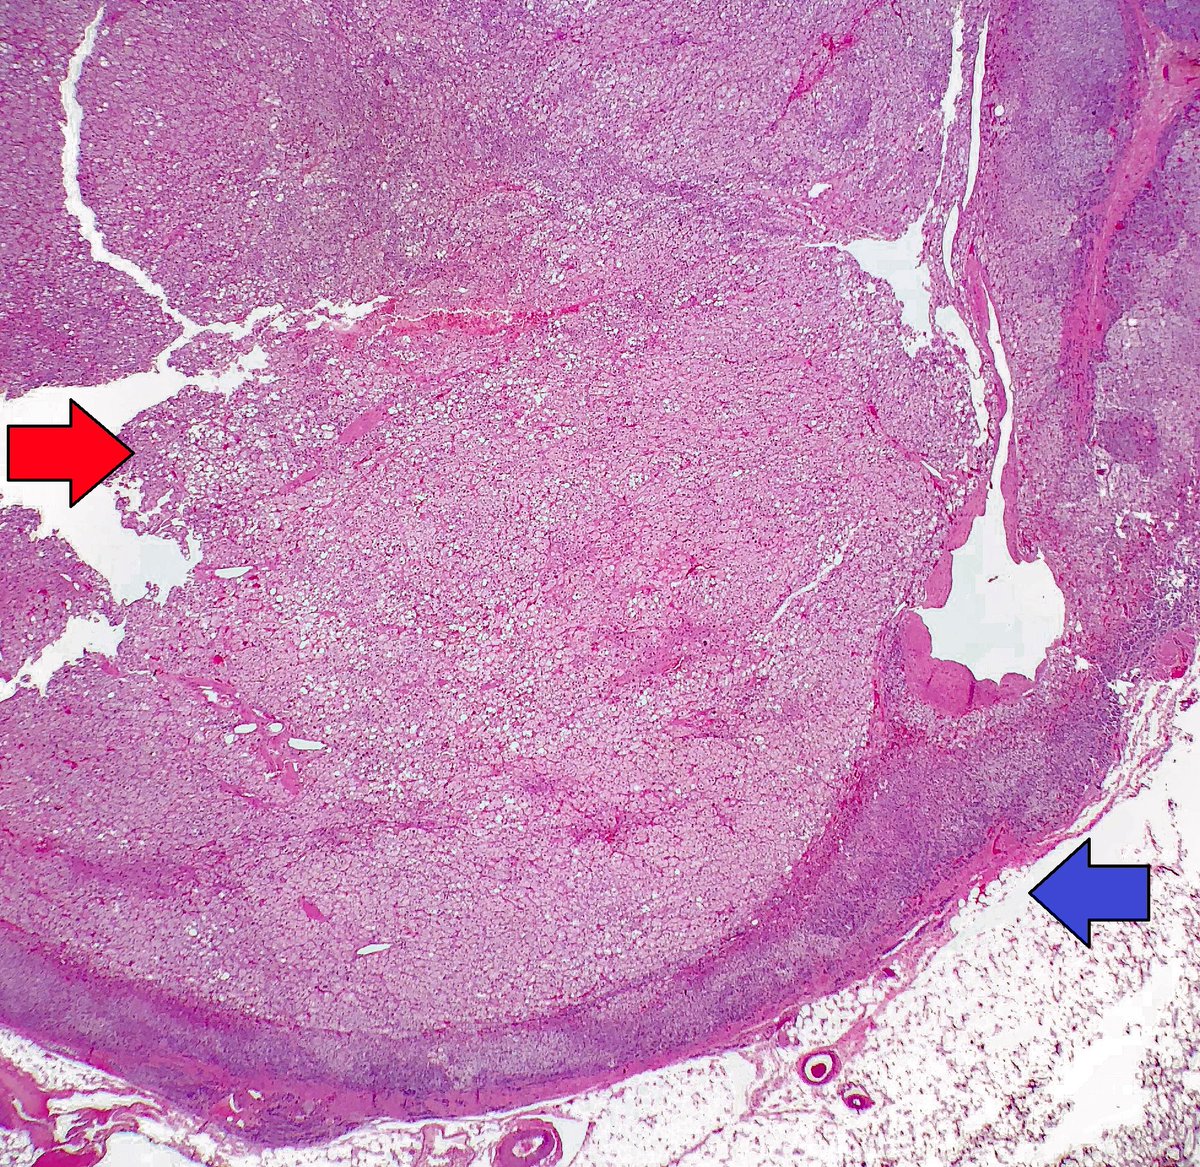

32-year-old woman with Conn syndrome who underwent a left adrenalectomy for an adrenal cortical adenoma. The gross photo shows the adenoma adjacent to a thin sliver of normal adrenal gland. Microscopic: adenoma (red arrow), residual adrenal (blue arrow).

#pathology#GrossPathpic.twitter.com/bYXyc3aAgB